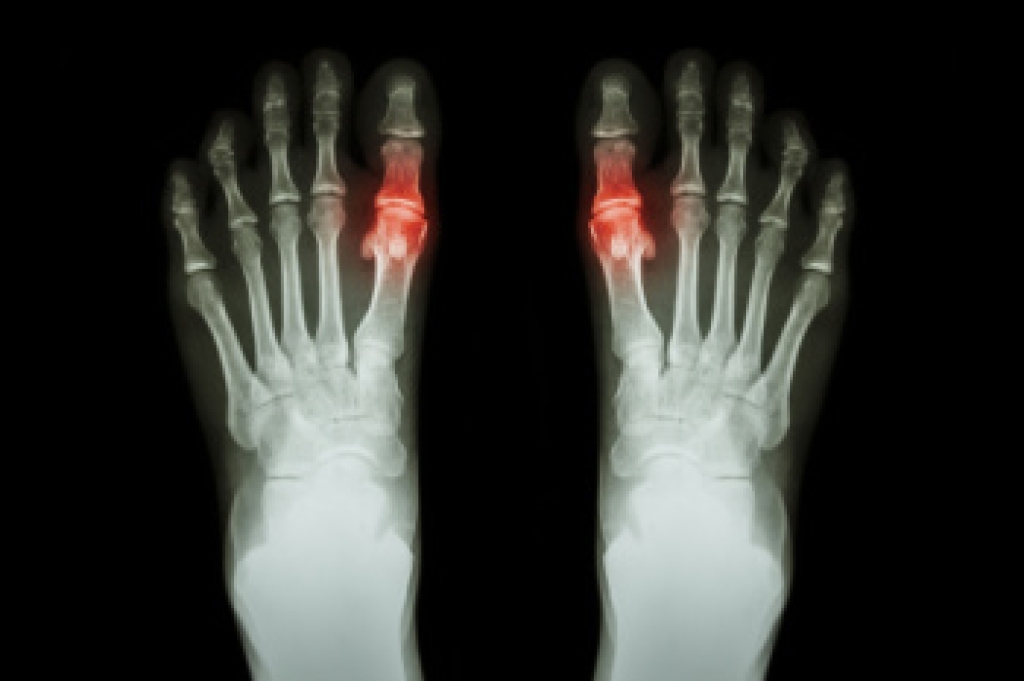

If you have any questions, please feel free to contact our office located in Lehi, UT . We offer the newest diagnostic and treatment technologies for all your foot care needs.